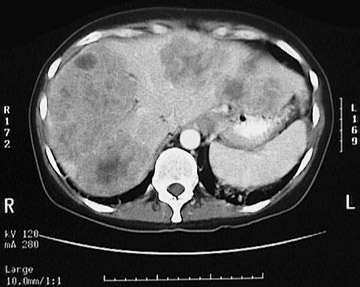

![]() | This computed tomographic (CT) scan without IV contrast of the abdomen demonstrates multiple darker mass lesions resulting in a markedly enlarged liver that extends from the right side to nearly the left side of the upper abdomen. These masses are metastases from a primary colonic adenocarcinoma. A normal sized spleen is seen at the lower left. Such mass lesions elevate the serum alkaline phosphatase, but the focal nature of the lesions means that the serum bilirubin is not elevated. |